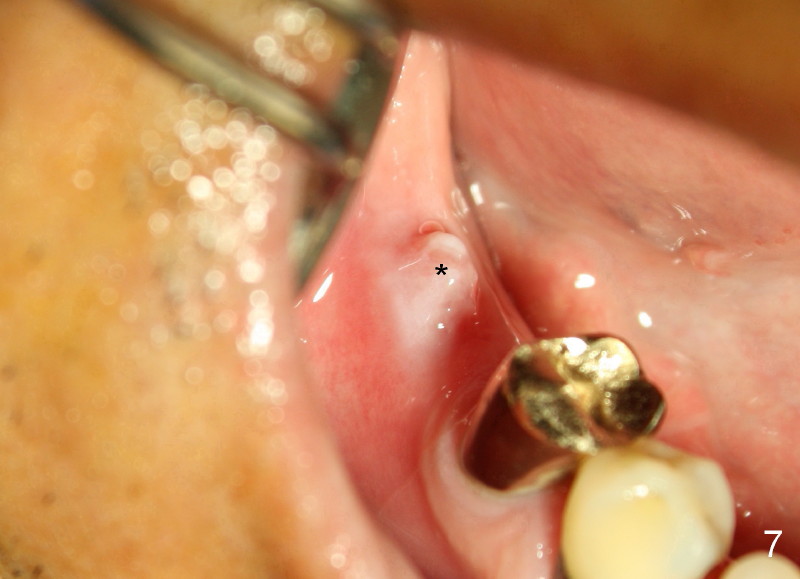

Unfortunately, there is bone resorption around the implant 3 months postop (Fig.6: >, as compared to Fig.4). Granulation tissue is present over the implant (Fig.7 *). The patient complains occasional pain and swelling after implant placement. Bone resorption is confirmed after removal of granulation tissue around the implant (Fig.8 *). After acid etch, Endogain (Fig.9 *, Straumann) is placed around the implant (P: healing plug). Flaps are approximated with 4-0 plain gut suture. Collagen membrane should have been used. Amoxicillin is prescribed, but the patient does not take it. It appears that bone graft to the sockets of #19 helps form an apparently continuous bone plate at the alveolar crest over the mesial (M in Fig.6') and distal (D) sockets, as compared to Fig.4'.